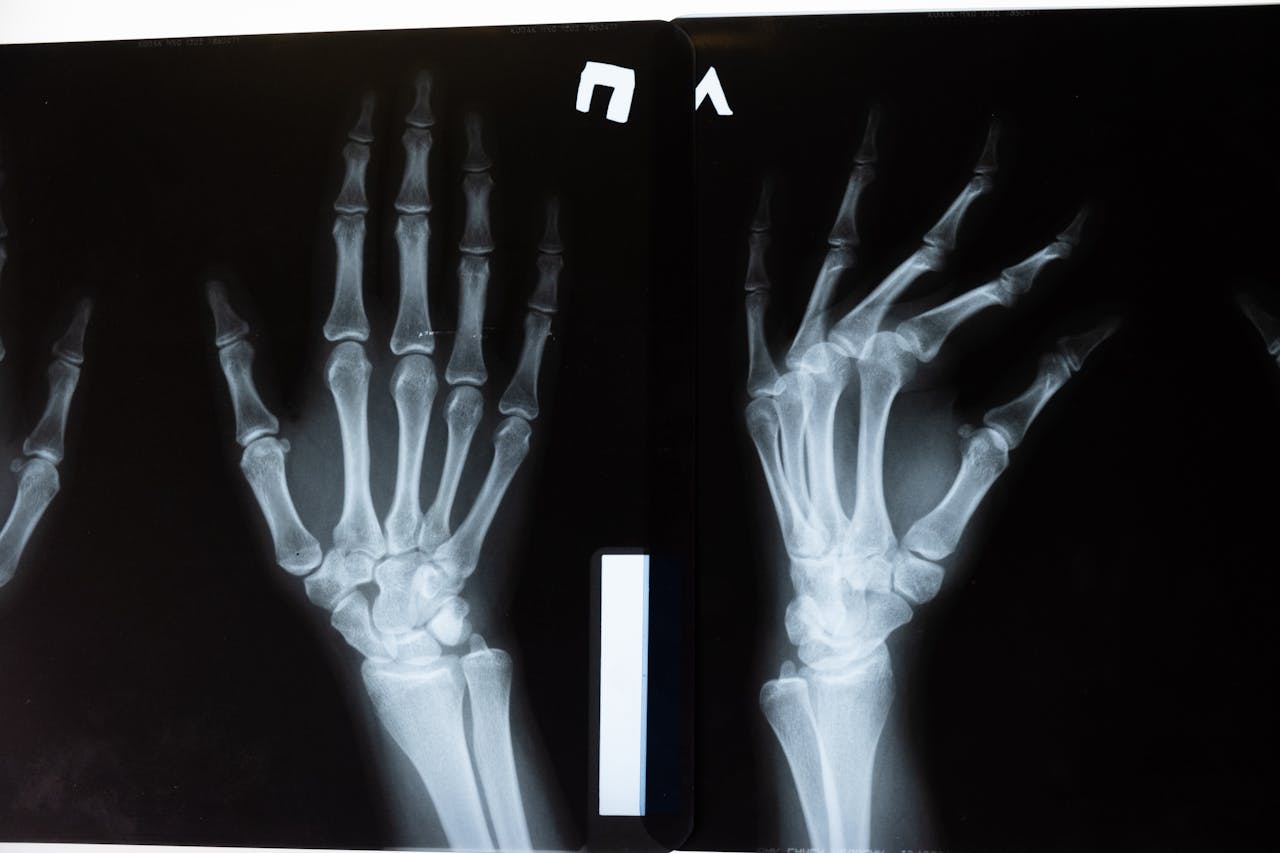

A síndrome do túnel do carpo ocorre quando o nervo mediano, que passa pelo túnel do carpo no punho, fica comprimido. Essa compressão provoca sintomas principalmente no polegar, indicador, mé

dio e metade do anelar.

O túnel do carpo é um espaço estreito formado por ossos e ligamentos. Se houver inflamação, inchaço ou qualquer aumento de volume no local, o nervo pode ser pressionado.

Como é feito o diagnóstico

O diagnóstico começa com uma boa história clínica e exame físico. Testes simples, como o teste de Phalen e o teste de Tinel, ajudam a identificar sinais de compressão do nervo mediano.

Exames complementares podem confirmar e avaliar a gravidade. A eletroneuromiografia mostra se há perda de condução do nervo. Ultrassom e ressonância ajudam a visualizar estruturas e possíveis causas locais.